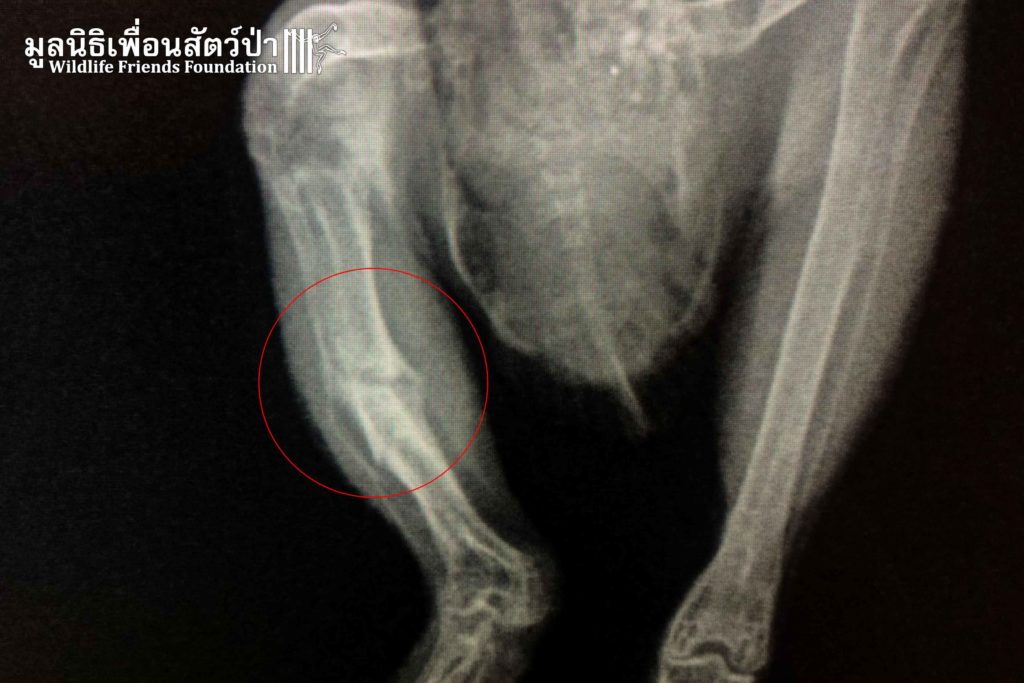

“ เฮ็ดวิก “ นกเค้าเเมว (Asian Barred Owlet) เกิดอุบัติเหตุรถชนกลางดึก ถูกทิ้งอยู่บนกลางถนน เเต่โชคยังเข้าข้างเมื่อมีพลเมืองดีมาช่วยไว้เเละได้ส่งต่อมูลนิธิเพื่อนสัตว์ป่าเพื่อเข้ารับการรักษา ผลตรวจ X-ray เเสดงให้เห็นว่ากระดูกหักที่ขาขวาซึ่งไม่ร้ายเเรง เฮ็ดวิก จะได้รับการดูเเลอย่างใกล้ชิดจากทีมสัตวเเพทย์จนกว่ากระดูกจะสมานกันจึงจะสามารถปล่อยคืนสู่ป่าได้

“Hedwig” an Asian barred owlet (Taenioglaux cuculoides) was found by the side of a busy road after being hit by a car. Luckily a concerned local found it and contacted WFFT for help. An X-ray examination showed a bone fracture on the right leg, which is not so severe so this has a good chance of healing. Hedwig will receive round the clock care from our vet team until the bone healed before it can be released.